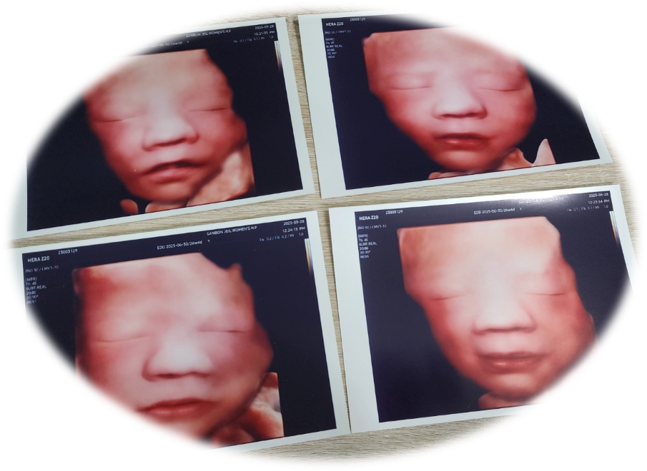

지난 26주 차에 찍었던 입체초음파 사진과 비교해 봤는데 무척 비슷하네요.

[왼쪽: 26주 차 입체초음파 사진, 오른쪽: 태어난 직후 사진]